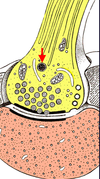

Two (2) parts of the axonal ending

- telodendron

- terminal boutons

What are the major organelles found in axon terminals

- mitochondria (ATP)

- synaptic vesicles (contain neurotransmitter molecules)

Components of synapses

- presynaptic membrane (with synaptic vesicles)

- synaptic cleft

- postsynaptic membrane

NB: can also have axo-spinous synapses

Neuromuscular Junction

- motor end plate is an enlarged terminal with:

- synaptic vesicles

- junctional folds

- enlarged synaptic cleft

- muscle sole plate

- end plate is covered by lemmocyte cytoplasm and basal lamina